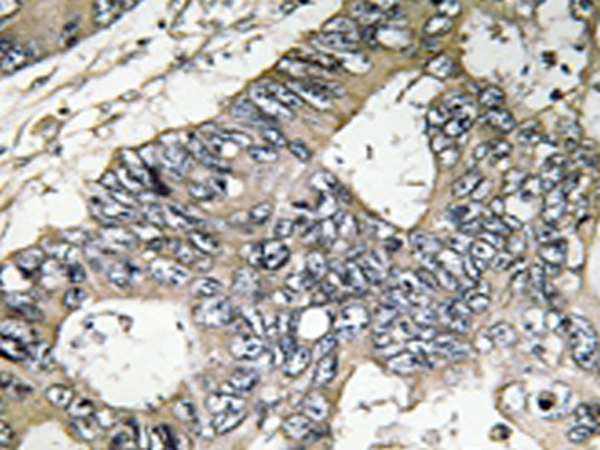

IHC positive control: |

Human colon carcinoma tissue |

IHC Recommend dilution: |

50-100 |